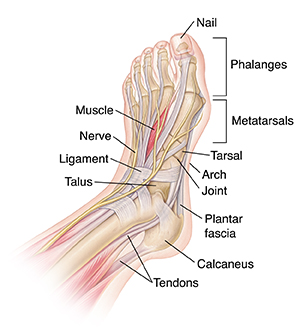

Anatomy of the Foot

The foot is one of the most complex parts of the body. It consists of 28 bones connected by many joints, muscles, tendons, and ligaments. The foot is prone to many types of injuries. Foot pain and problems can cause pain and inflammation, limiting movement.

Muscles contract and relax to move the foot.

Tendons are tough fibers that connect muscles to bones.

Ligaments are fibrous strands that connect bones.

Nerves travel throughout the foot, providing feeling.

Nails protect the tips of the toes.

Phalanges are the toe bones.

Metatarsals are the bones between the toes and the ankle bones.

Tarsals are bones of the rear foot (hindfoot) or middle foot (midfoot).

The talus is one of the ankle bones.

The calcaneus is the heel bone.

The arch is formed by bones and held in place with ligaments.

Joints are the meeting points between two bones. They are lined with cartilage. Cartilage is smooth tissue that allows joints to move easily.

The plantar fascia is a sheet of fibrous tissue that supports the arch and encloses muscles there.